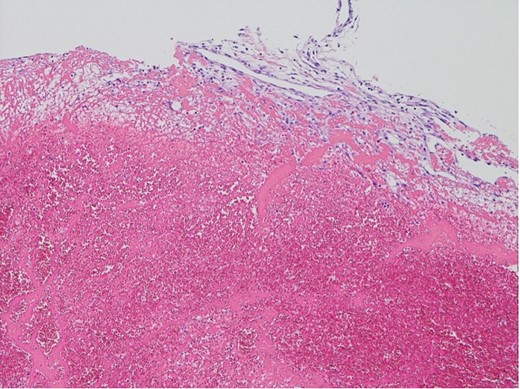

The surgical procedure employed a median sternotomy, with creation of cardiopulmonary bypass via cannulation of the ascending aorta and right atrium. After cross-clamping, cold antegrade cardioplegia was administered. Upon aortic valve exposure, a 2 × 2-cm vegetation was noted on the noncoronary cusp (Figs 2 and 3). The vegetation was quickly removed, and the noncoronary cusp was preserved. Following a 50-min bypass time, with a 35-min cross-clamp time, the patient was successfully weaned off bypass with minimal inotropic support. A portion of the vegetation was sent for culture; however, no bacterial or fungal growth was detected. Further histopathologic examination revealed a fibrin-rich thrombus containing red blood cells with organization at the periphery (Fig. 4).

Histopathological appearance of the vegetation: mainly fresh and organizing thrombus, consisting of fibroblast and capillary hyperplasia in the upper part of the specimen (hematoxylin and eosin staining, ×100).

NBTE frequently involves a systemic hypercoagulable state, including malignancy, systemic lupus erythematosus, antiphospholipid syndrome, polycythemia, and proteins C and S deficiencies [1–4]. The precise trigger for thrombus formation remains unclear. However, immune complex or mechanical endothelial injury sets in motion a cascade leading to platelet aggregate and fibrin strand deposition on cardiac structures [4, 5, 8]. Histologically, a fresh and organized thrombus, characterized by fibroblast and capillary hyperplasia, is observed within the vegetation adhering to the valve surface. Our case was diagnosed as NBTE on the basis of the abovementioned histological features; however, the cause of thrombus formation was not identified. Conversely, of note, vegetation developed in the aortic valve following CAG. As the right coronary artery originated from the left coronary apex, catheterizing the right coronary artery was difficult. Attempting multiple cannulations may have damaged the endocardium of the aortic valve. A previous case report showed aortic valve vegetation following radiofrequency catheter ablation of a left-sided accessory pathway via a retrograde approach [9]. Mechanical stimulation by the catheter may have induced thrombus formation.